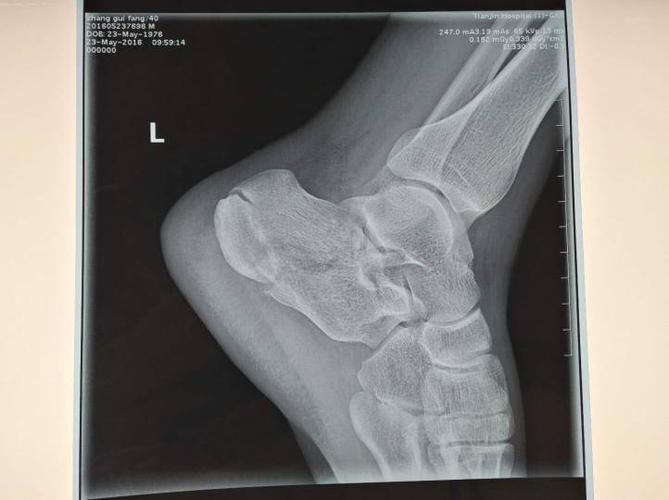

跟骨骨折切开复位钢板内固定术

病例讨论跟骨骨折

跟骨骨折